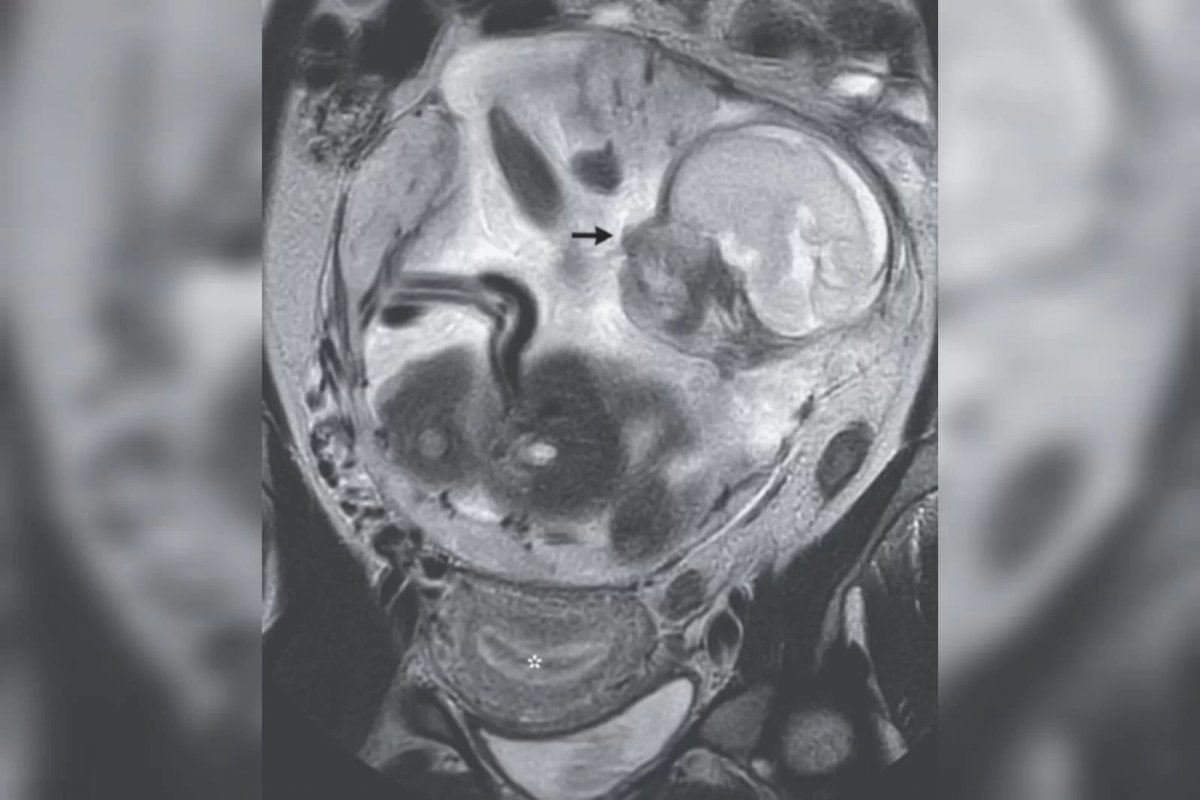

Uma mulher de 37 anos descobriu estar grávida, em um caso raro de gestação ectópica (quando ela ocorre fora do útero), ao buscar atendimento médico para as cólicas intensas que vinha sentindo há mais de dez dias. O caso ocorrido na França foi revelado por um artigo publicado no New England Journal of Medicine, que também trouxe imagens dos exames realizados na paciente.

Segundo os profissionais que atenderam a francesa, a mulher vinha reclamando de progressivas dores abdominais e inchaço na barriga. Ao realizar alguns exames, foi descoberto que ela estava grávida de 23 semanas. O feto ainda estava se desenvolvendo em um saco gestacional entre o estômago e o intestino dela.